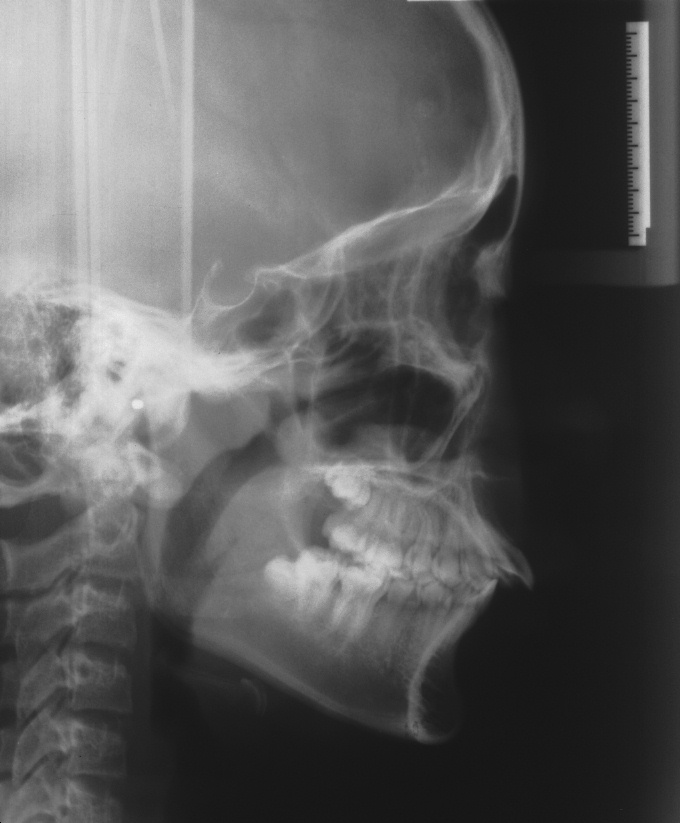

치료 전 사진입니다.